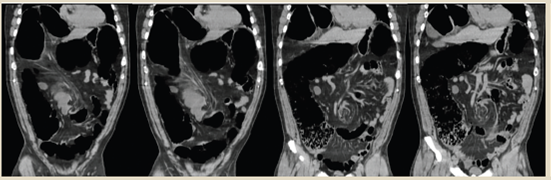

En la tomografía simple de abdomen en reconstrucción coronal se observó dilatación marcada de asas de todo el marco colónico con predominio a nivel de colon sigmoides, así como desplazamiento y sobreposición de este hacia flanco e hipocondrio derecho, con diámetro transverso máximo de 17 cm, niveles hidroaéreos y material de residuo en colon ascendente. En la topografía de la raíz del mesenterio se apreció el signo tomográfico del “remolino” o “whirpool” identificando paquete vascular mesentérico envolviéndose junto al mesenterio (figura 15). Confirmando el diagnóstico de vólvulo de sigmoides se procedió a realizar tiempo quirúrgico identificando como hallazgos colon sigmoides distendido con diámetro máximo de 18 cm, rotación a nivel de transición de colon descendente y sigmoides en contra de las manecillas del reloj, sin datos de compromiso vascular ni perforación (figura 16), elementos de fijación (mesocolon sigmoides y fascia de Toldt) redundantes (figura 17). Se completó tiempo quirúrgico mediante realización de procedimiento de Hartmann con colostomía terminal.

Figura 15 TAC simple de abdomen (reconstrucción coronal). Dilatación marcada de asas de todo el marco colónico con predominio a nivel de colon sigmoides, desplazamiento y sobreposición de este hacia flanco e hipocondrio derecho, diámetro transverso máximo de 17 cm. En la topografía de la raíz del mesenterio se aprecia el signo tomográfico del “remolino” o “whirpool” identificando paquete vascular mesentérico envolviéndose junto al mesenterio